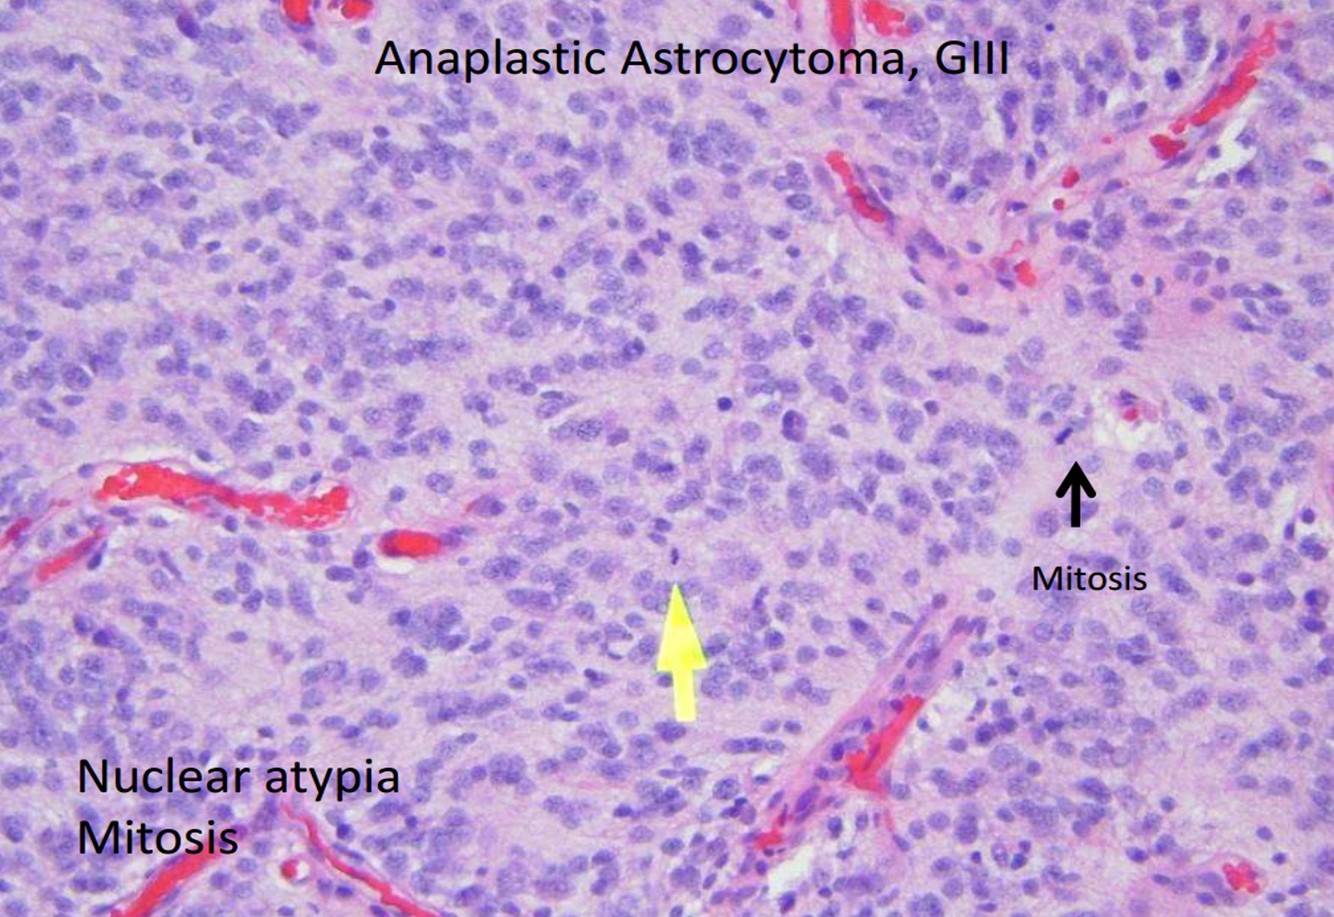

- Anaplastic astrocytoma

- WHO Grade III:

- WHO Grade III: anaplastic astrocytoma

- Anaplastic astrocytoma: 45 y/o